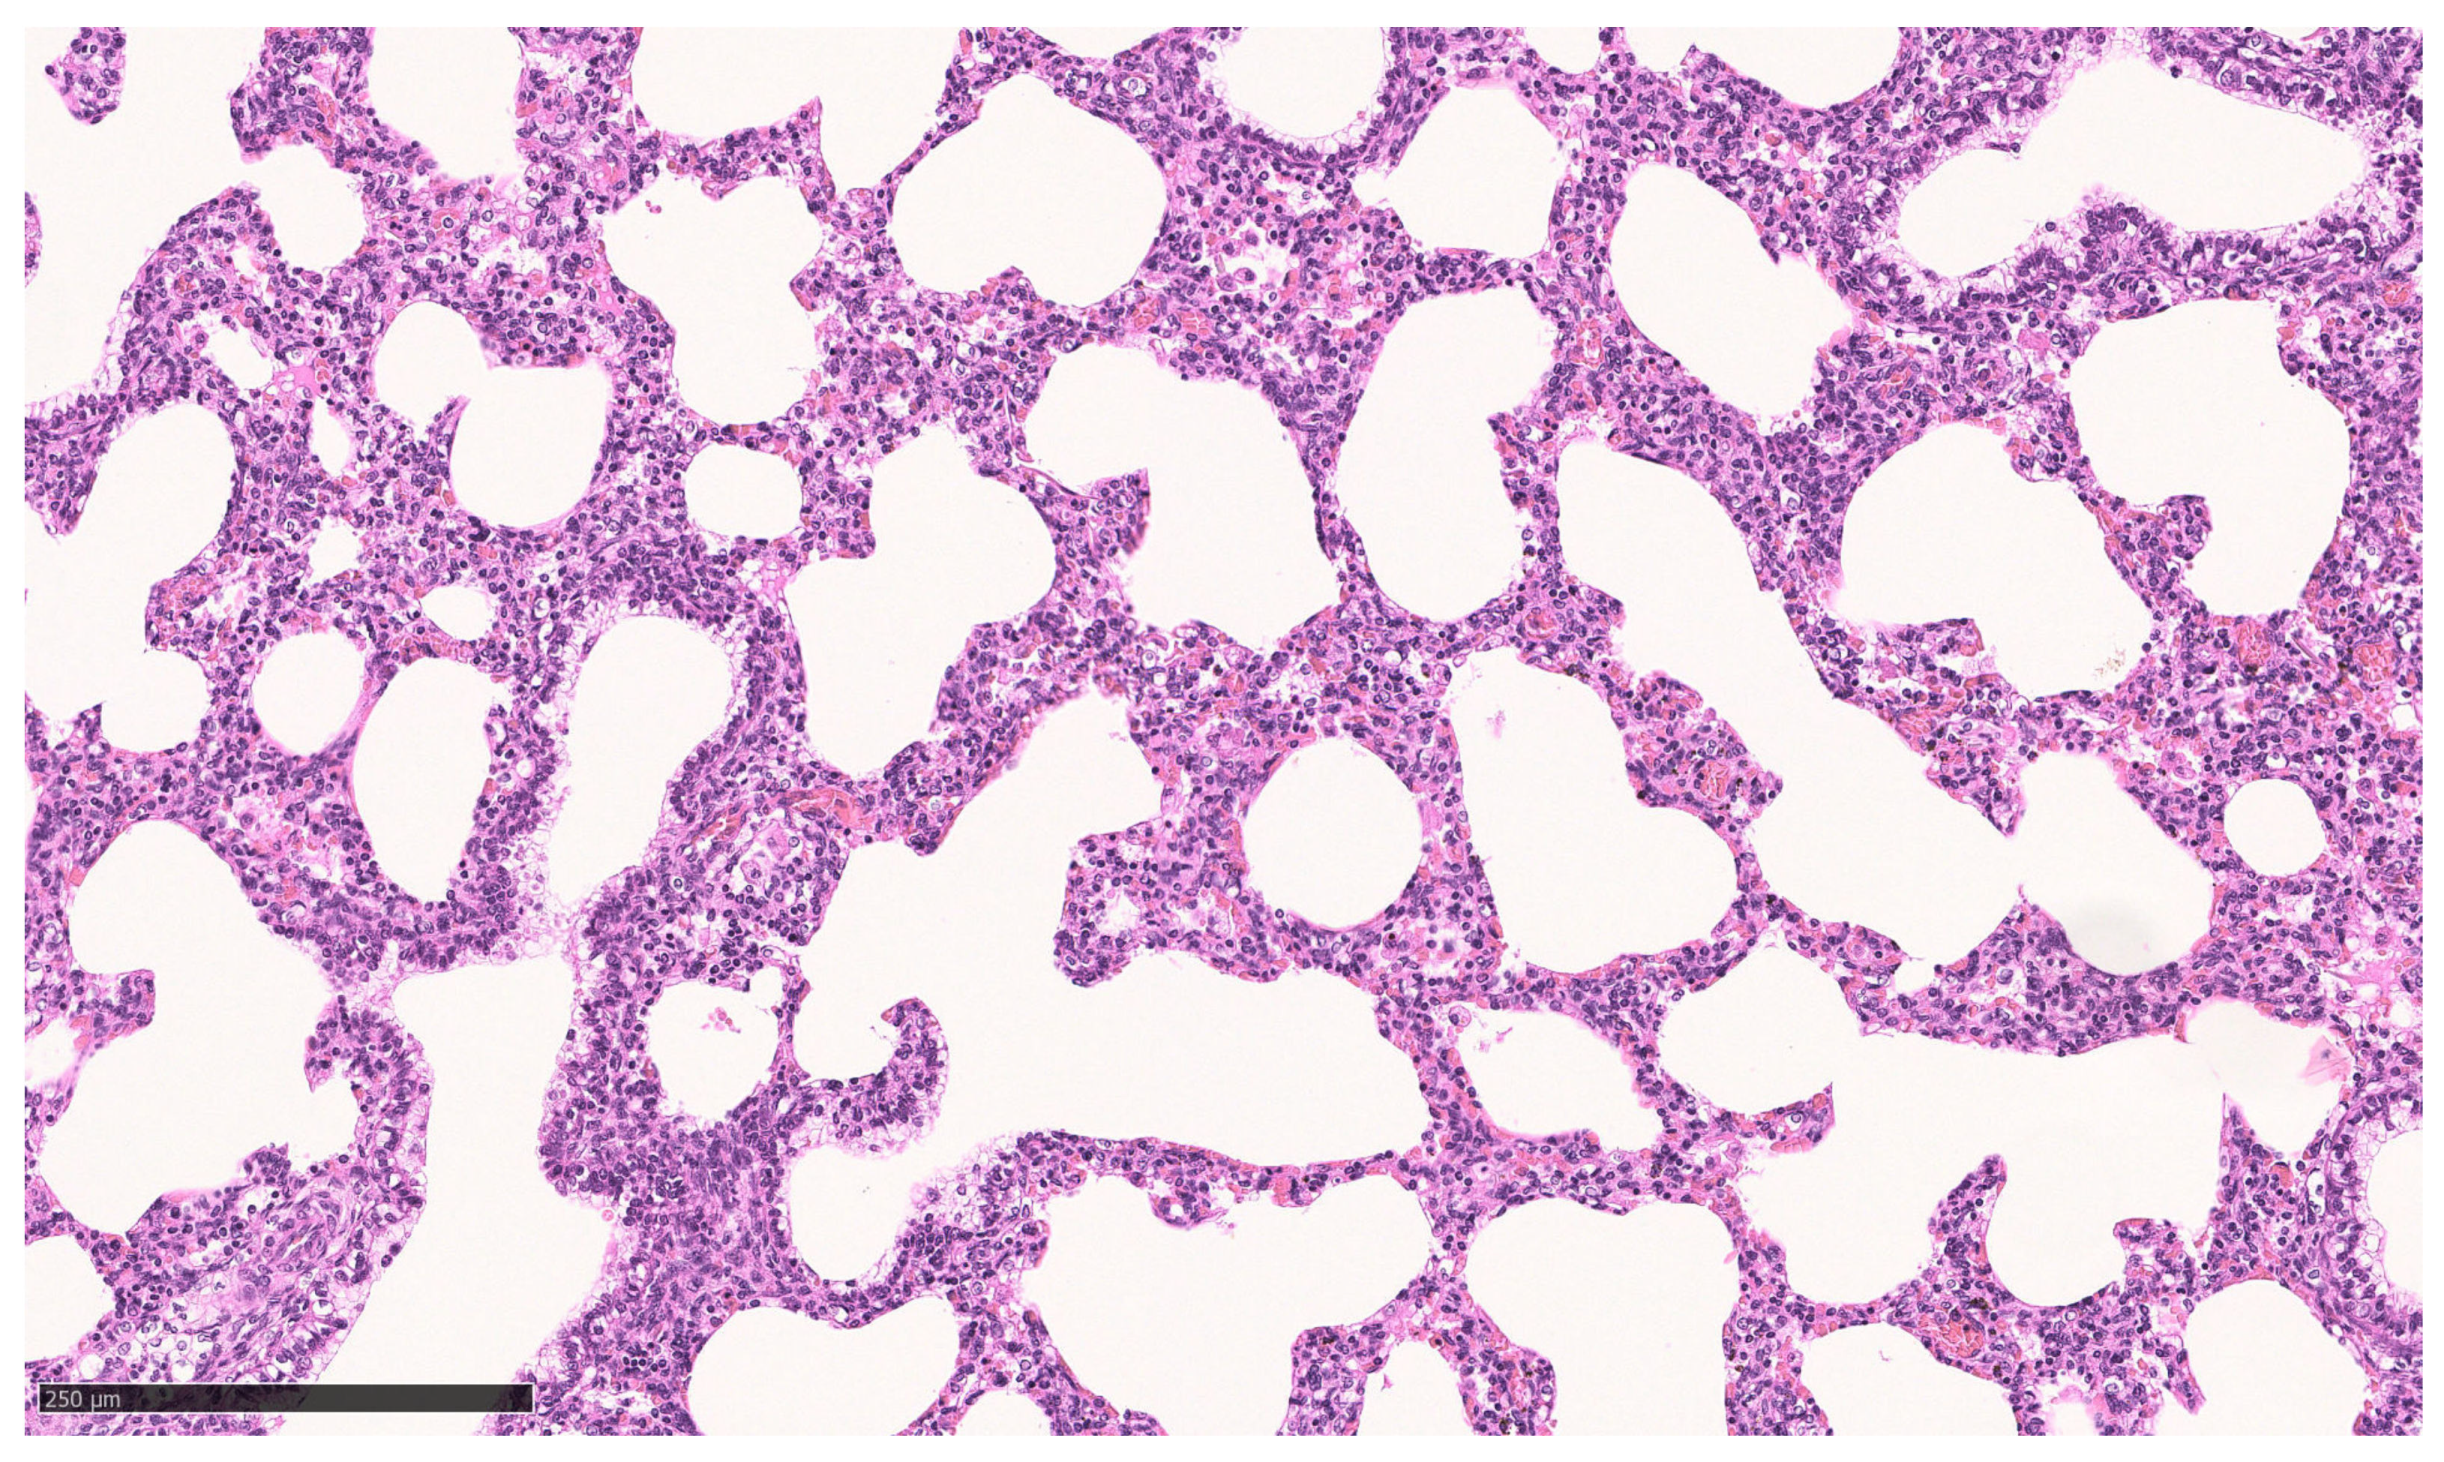

For ethical reasons, no vital born, alive pups were euthanized for microscopic tissue examination. Instead, the lungs of pups that died between 0.5 and 48 h p.n. were used for comparison (n = 3). All of these neonates suffered from respiratory problems (neonatal respiratory distress syndrome, NRDS) from the beginning of the postnatal period. A histopathologic examination of their lungs revealed either low-grade ventilated or largely nonventilated (atelectatic) lung tissue except for bronchioles and bronchi. In some localizations, aspirated squames or other amniotic fluid components (e.g., meconium) were found, as well as exfoliated pneumocytes in terminal sacculi and bronchioles (Figure 6). However, some areas of the pulmonary tissue showed moderately aerated lung saccules and dilated bronchioles (Figure 7).

Figure 7. Lung, dorsal lobe of vital pup after death 48 h p.n. Lung saccules and bronchioles are moderately dilated; Bar: 250 µm.